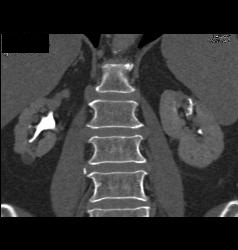

Transitional Cell Cancer (TCC) of Left Kidney- See CT Urogram and Full Sequence of Images